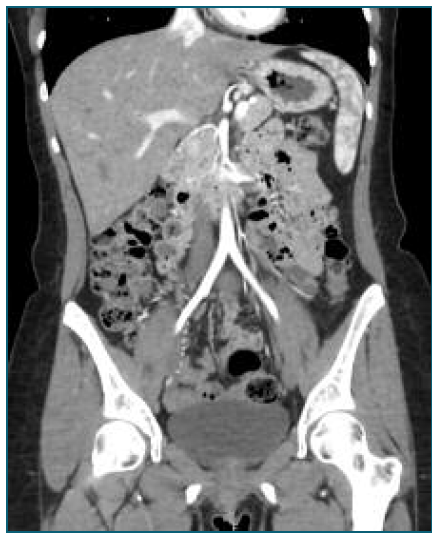

Initial laboratory tests revealed a hemoglobin drop from 11 g/dL in late pregnancy to 9.3 g/dL, suggesting mild postpartum anemia. A renal-bladder ultrasound and an abdominal X-ray imaging (Figure 1) were performed, excluding urinary and intestinal complications. Persistent pain along with an episode of lipothymia prompted an urgent abdominopelvic contrast-enhanced CT-scan, revealing a 19 cm retroperitoneal hematoma in the left flank and iliac fossa (Figure 2). Additionally, a 7 mm pseudoaneurysm in the LOA was identified as the source of intermittent hemorrhage (Figure 3A).

Figure 1 Abdominal X-ray performed due to suspected intestinal obstruction, revealing displaced and distended intestinal loops with obscuration of the psoas muscle contour. These findings are nonspecific and have low sensitivity for detecting retroperitoneal hemorrhage, notably in low- to moderate-volume hematomas.